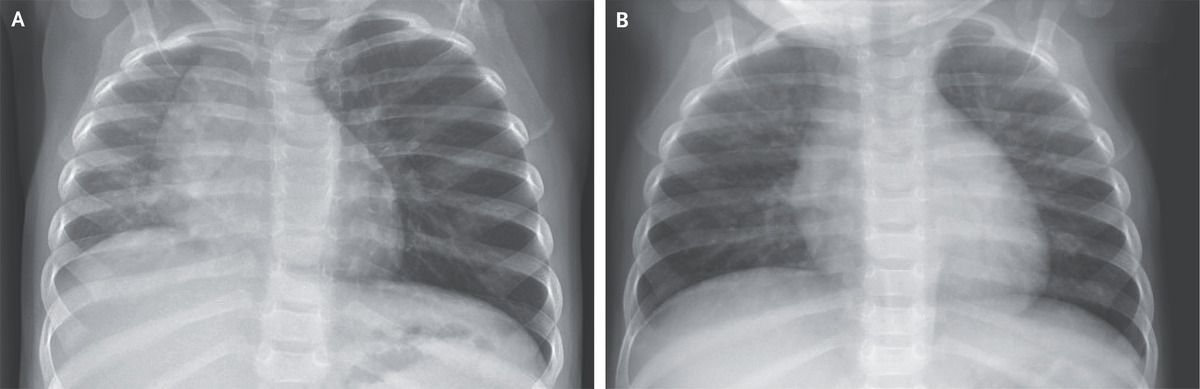

A healthy 12-month-old girl was brought to the emergency department with a 4-hour history of coughing and stridor. Four hours earlier, she had choked while eating. Her respiratory rate was 38 breaths per minute, and her oxygen saturation was 98% while she was breathing ambient air. On examination, she appeared well. No cough or stridor was observed. Crackles and wheezing were heard in the right lung, and the left lung was clear. A chest radiograph showed opacification and volume loss in the right lung, rightward shift of the mediastinum, and hyperinflation of the left lung (Panel A). Given the abnormal radiographic appearance of the right lung, there was concern about right-airway obstruction. However, during rigid bronchoscopy, a foreign body was removed from the left mainstem bronchus. Partial airway obstruction in the left mainstem bronchus had resulted in hyperinflation on that side, with passive atelectasis and opacification on the right side. Foreign-body aspiration in children is potentially life-threatening. It is important to note that chest radiographs may appear normal when radiolucent objects are aspirated. High clinical suspicion of foreign-body aspiration should prompt bronchoscopy in order to avoid acute and chronic complications. A repeat chest radiograph in this patient was normal (Panel B), but her course was complicated by pneumonia, which abated with antimicrobial treatment.